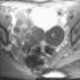

Struma ovarii

A struma ovarii (literally: goitre of the ovary) is a rare form of monodermal teratoma that contains mostly thyroid tissue, which may cause hyperthyroidism.Despite its name, struma ovarii is not restricted to the ovary. The vast majority of struma ovarii are benign tumours; however, malignant tumours of this type are found in a small percentage of cases. [Source: Wikipedia ]